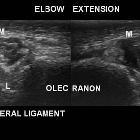

Ultrasound

Thin hypoechoic mass superficial to the ulnar nerve. May also demonstrate underlying ulnar nerve changes (thickening and edema) suggestive of cubital tunnel syndrome .